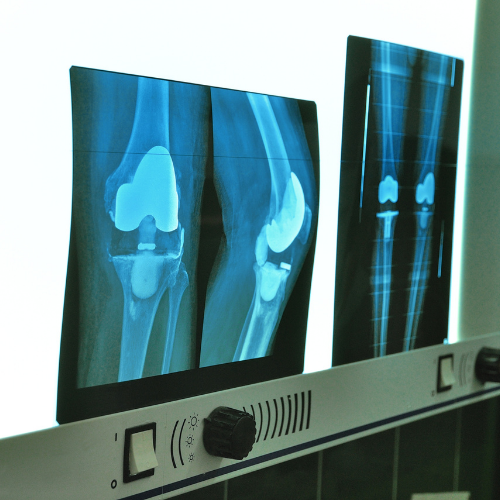

Artroscopia della Spalla e del Ginocchio

L’artroscopia della spalla e del ginocchio è una tecnica chirurgica minimamente invasiva che consente al Dott. Edoardo Cristalli di trattare con precisione diverse problematiche articolari. Questa metodica è particolarmente indicata per risolvere lesioni della cartilagine, lesioni ai legamenti o alla cuffia dei rotatori della spalla e danni alle articolazioni del ginocchio, come le rotture del menisco o dei legamenti crociati. Grazie a piccoli incisions e l’uso di strumenti specializzati, l’artroscopia permette un recupero rapido, con un minor dolore post-operatorio e un ritorno veloce alle normali attività.